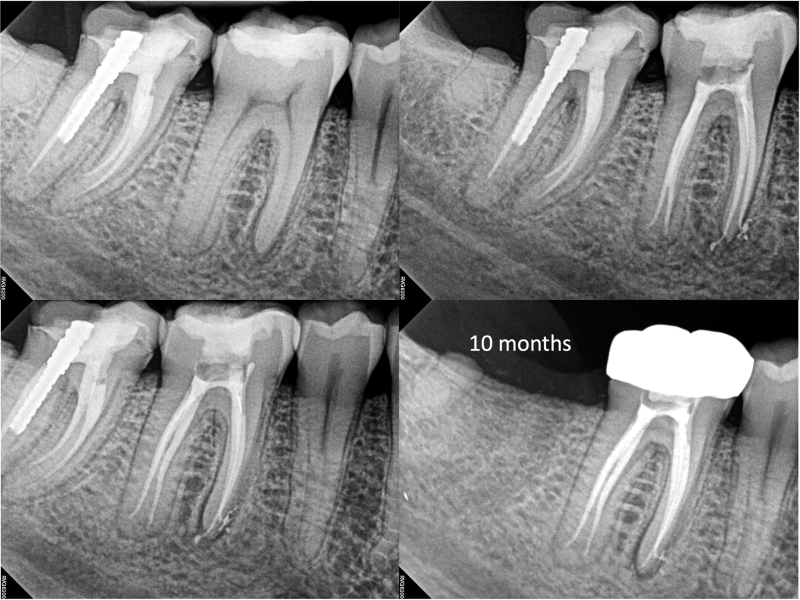

Middle Mesials in MN Molars with 10 Months Healing Evidence